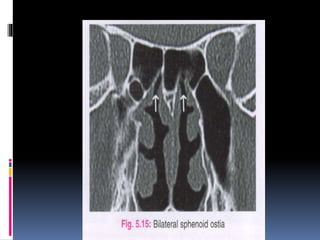

 Sphenoid sinus is seen.

 The sphenoid dominance should be noted when

the intersphenoid septum is asymmetrical.

 Sphenoid sinus ostium may also be visualised ,

though it is better seen in saggital cuts.